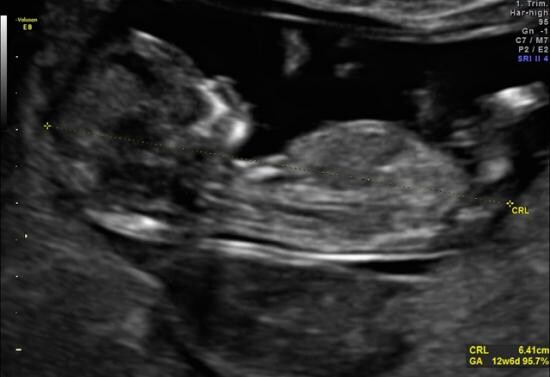

- badanie I trymestru (USG + test II z krwi matki) wykonywane między 11-14 t.c.

Celem badań jest wykrywanie wad wrodzonych u płodu, oszacowanie ryzyka wystąpienia nieprawidłowości chromosomowych u płodu na podstawie tzw. markerów.